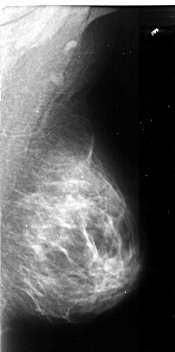

A_1105_1.RIGHT_MLO

RIGHT_MLO LINES 5266 PIXELS_PER_LINE 2611 BITS_PER_PIXEL 16 RESOLUTION 42 NON_OVERLAY